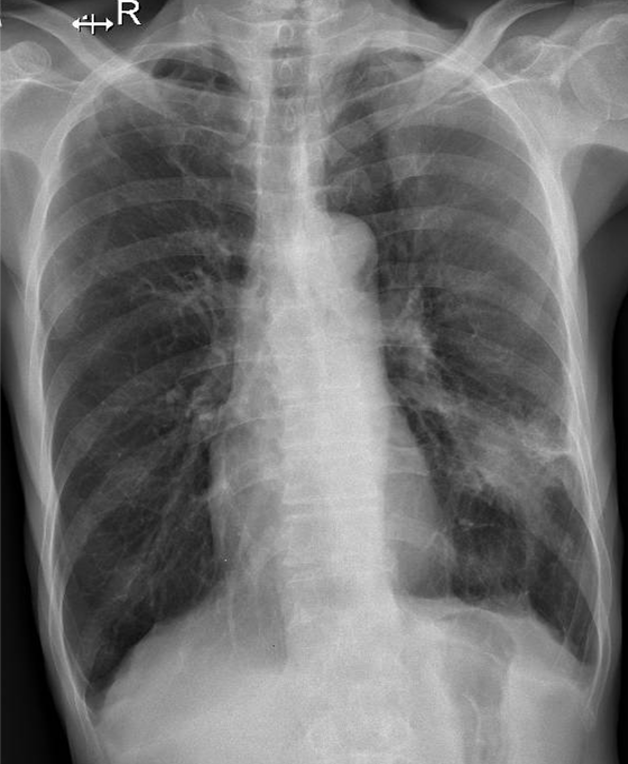

Hãy phân tích tình huống nam 65 tuổi

1-U thùy dưới phổi (T) 2-Khí phế thũng rải rác hai phổi 2-Dày dính màng phổi (T)